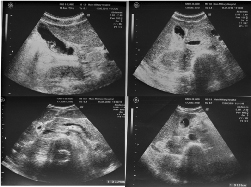

Результати повторного УЗД органів черевної порожнини (рисунок): печінка збільшена (вертикальний розмір лівої частки 120 мм, правої — 170 мм), контури гладкі. Жовчний міхур 70×26 мм, стінка потовщена до 5 мм, пошарована, в середній третині перегин, у просвіті осад, що заповнює половину просвіту жовчного міхура. Загальна жовчна протока 6 мм. Підшлункова залоза в ділянці голівки 32 мм, в ділянці тіла — 18 мм, контур гладкий, ехогенність тканини підвищена. Селезінка не збільшена. У черевній порожнині невелика кількість вільної рідини. У проекції воріт печінки численні збільшені лімфатичні вузли діаметром до 3 мм. Візуалізували також збільшені заочеревинні лімфатичні вузли діаметром до 10 мм.

Рисунок. УЗД органів черевної порожнини хворого О. на 3-й день лікування